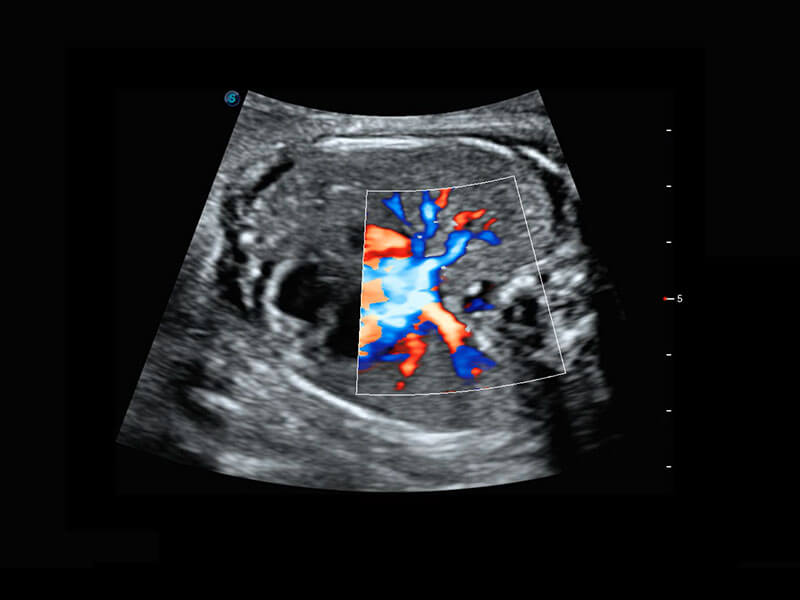

四腔切面

四腔心血流

右室双出口

胎心容积成像